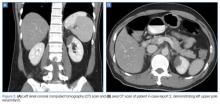

A polymerase chain reaction (PCR) test confirmed a diagnosis of dengue, with a positive dengue type-4 (DEN-4) serotype detection. Supportive care was initiated, and the patient was admitted to the inpatient hospital for continued treatment. He was discharged home on hospital day 5; however, he returned to the ED later that day with increasing headache and left flank pain. Work-up included axial and coronal computed tomography scans of the abdomen and pelvis, which revealed hematuria and a left upper pole renal infarction surrounded by mild perinephric fat stranding (Figure 2a and 2b) with maintenance of left renal artery/vein patency.